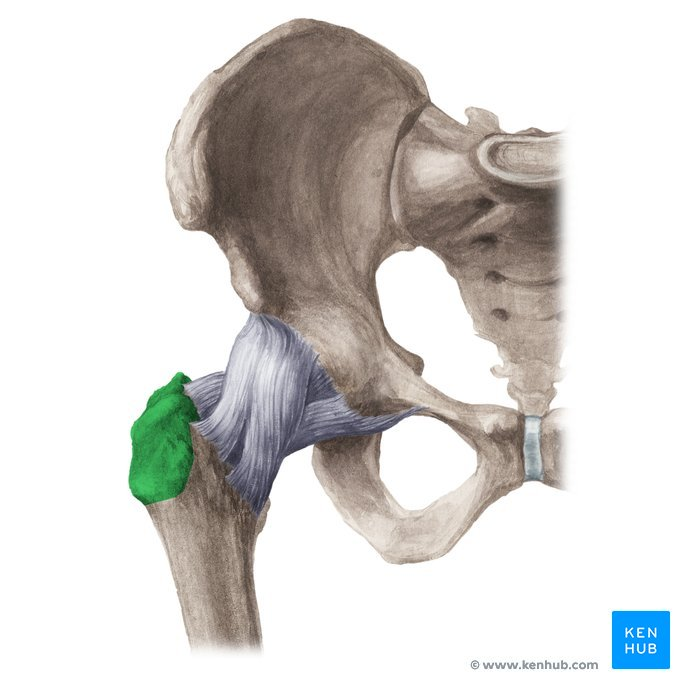

Greater Trochanter of the Femur